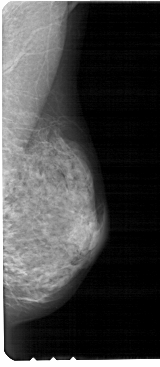

A_1897_1.LEFT_CC

LEFT_CC LINES 5071 PIXELS_PER_LINE 2311 BITS_PER_PIXEL 12 RESOLUTION 43.5 OVERLAY